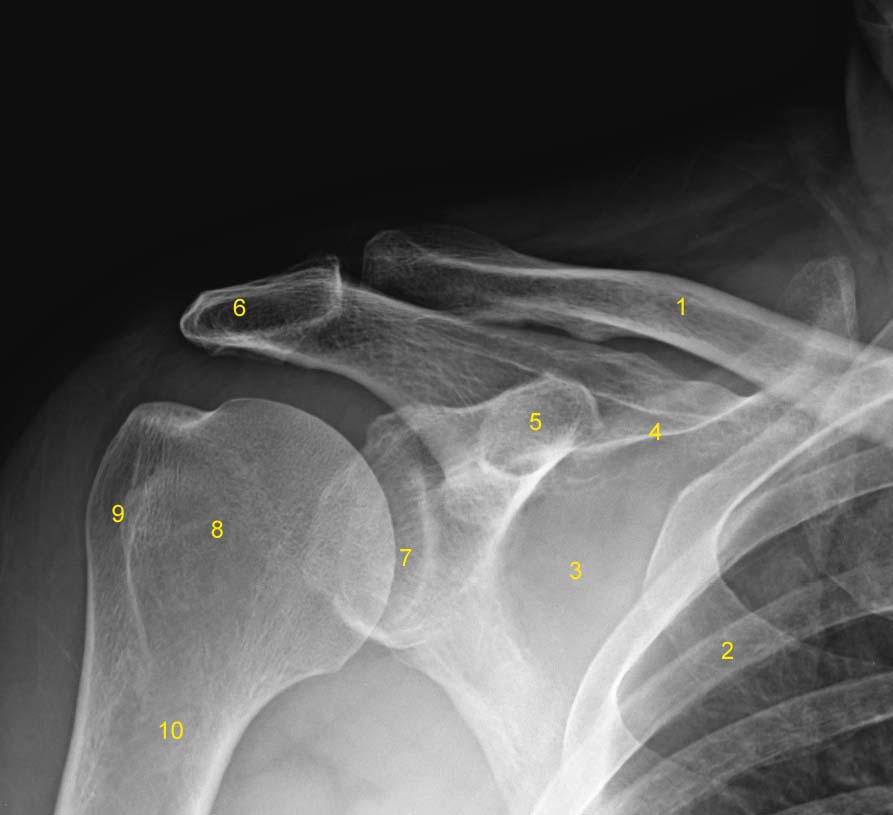

Shoulder x-ray (AP)

Labeled Study

Legend